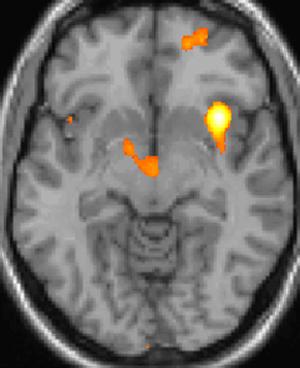

양전자 방출 단층 촬영술(PET) 이미지 1: 통증 중 활성화되는 뇌 영역

양전자 방출 단층 촬영술(PET) 이미지 2: 통증 중 활성화되는 뇌 영역

양전자 방출 단층 촬영술(PET) 이미지 3: 통증 중 활성화되는 뇌 영역

복셀 기반 형태 계측법 이미지 1: 뇌 영역의 구조적 차이

복셀 기반 형태 계측법 이미지 2: 뇌 영역의 구조적 차이

복셀 기반 형태 계측법 이미지 3: 뇌 영역의 구조적 차이

실제로 양전자 방출 단층 촬영술(PET) 스캔 연구 결과, 군발 두통 발작 중에 통증이 없을 때와 비교하여 시상하부의 특정 영역이 활성화되는 것이 관찰되었다. 또한, 복셀 기반 형태 계측법(VBM)을 이용한 연구에서는 군발 두통 환자와 그렇지 않은 사람 사이에 뇌 구조를 비교했을 때, 시상하부의 일부 영역에서 구조적인 차이가 발견되기도 했다.[35] 이러한 영상 연구 결과는 시상하부가 군발 두통의 발생과 관련이 깊다는 가설을 뒷받침한다.